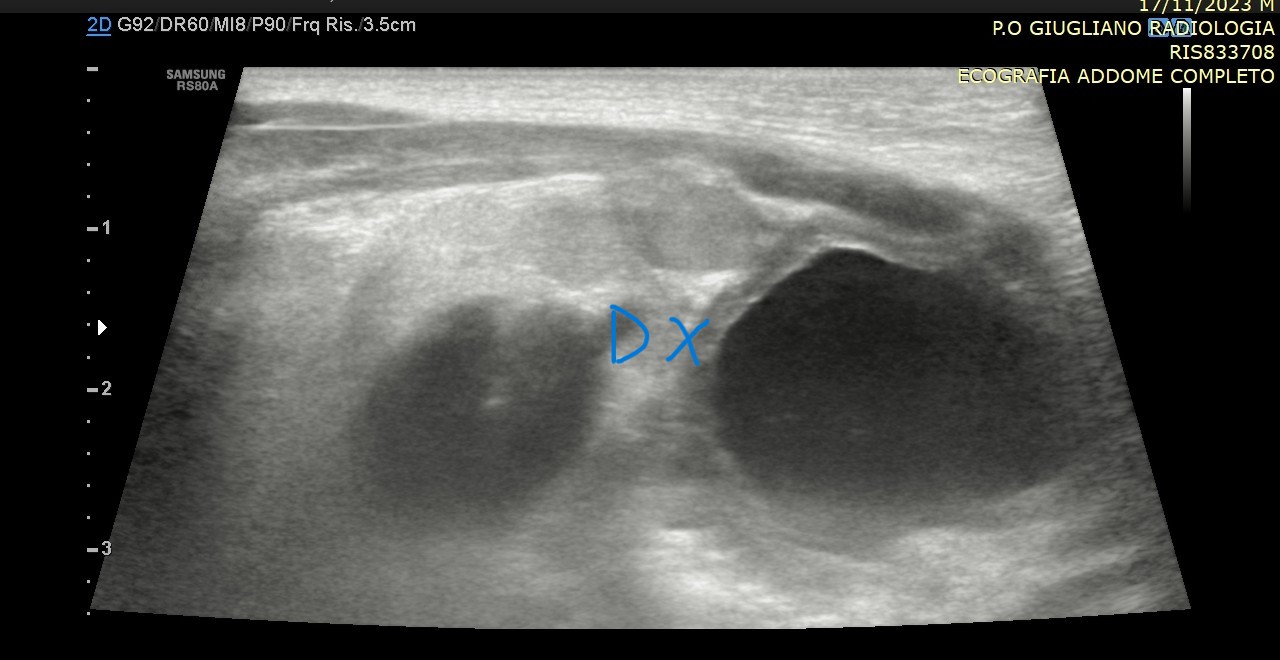

La diagnosi si basa innanzitutto sull’esame obiettivo del neonato o del bambino, affiancato quando necessario da indagini ecografiche o laparoscopiche. Il trattamento di scelta è chirurgico, tramite orchidopessi, e dovrebbe essere eseguito precocemente, idealmente tra i 6 e i 12 mesi di età, per ridurre al minimo i rischi futuri.